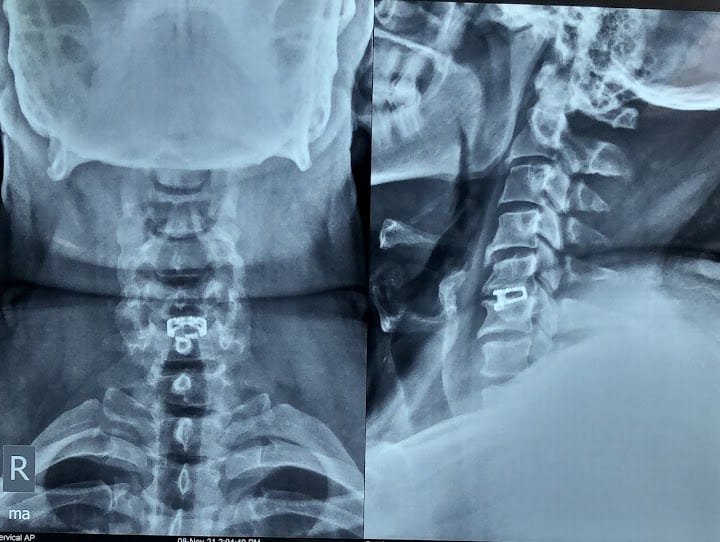

Spine Surgery

Dr. Rahul is a highly experienced spine surgeon specializing in diagnosing and treating spinal conditions. He performs a wide range of surgical options for spinal conditions, including minimally invasive techniques, spinal fusion, and disc replacement.

Minimal invasive spine surgery / endoscopic spine surgery

Endoscopic spine surgery offers many benefits over traditional open surgery, including smaller incisions, less blood loss, and faster recovery times. Dr. Rahul is the go-to specialist for endoscopic spine surgery in the area.